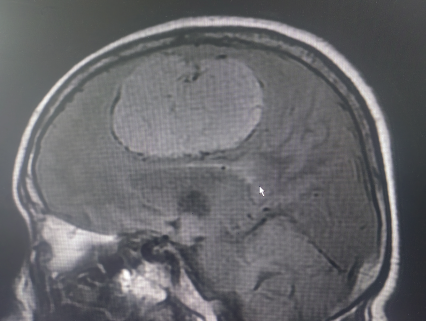

患者系中年女性,因出现偏侧肢体活动不灵和头痛症状,经检查发现颅内大脑镰旁长有一直径7cm的巨大肿瘤。肿瘤位于大脑的运动功能区,血供丰富,这一区域的手术风险极大。在决定手术治疗之前,神经外科医生与患者家属进行了充分的沟通,详细解释了手术的必要性、可能的风险和并发症,包括出血、感染、血管和神经损伤以及脑功能障碍等。家属在充分了解情况后,同意进行手术。面对这一复杂病例,我院迅速组织了由神经外科、麻醉科、心内科、输血科等多个科室的专家团队进行会诊,共同制定了先介入栓塞,再手术切除的治疗方案。

神经外科血管介入组曲友直副教授、崔刚副教授和高攀主治医师对肿瘤进行了瘤栓塞治疗,有效减少了肿瘤的血供,为后续的手术切除降低了风险。栓塞治疗后,神经外科王睿智副主任、高李贵副教授和董全主治医师在麻醉科、心内科、输血科等科室的全力配合下,凭借精湛的医术和丰富的临床经验,成功为患者切除了病变。手术过程中,麻醉科吕建瑞主任团队全程监控患者的生命体征,确保麻醉安全;心内科团队随时准备应对可能出现的心脏问题;输血科团队则确保充足的血液供应,以备不时之需。多学科的通力合作,为手术的成功提供了坚实的保障。